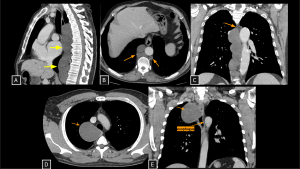

Fig 4: Cases 2 and 3 – Thoracic duct lymphocele and Esophageal Duplication Cyst:

An asymptomatic patient undergoing staging for colon neoplasia demonstrated, on chest computed tomography, an extensive elongated hypoattenuating, non-enhancing formation within the visceral mediastinum (A), communicating with small dilatations of the lumbar lymphatic ducts (arrows in B), consistent with a thoracic duct lymphocele. The lesion was secondary to an obstructive lipoma located in an anterior paravertebral position at the level of the aortic arch (arrow in C).

Panels D and E demonstrate a well-circumscribed cystic lesion in the visceral mediastinum (arrows) with broad contact with the right esophageal wall. The lesion remained stable compared to prior exams. Surgery confirmed an Esophageal Duplication Cyst.

Thoracic Duct Lymphocele SYSTEMATIC APPROACH: 1. Age: Adults (secondary to obstruction/trauma) | 2. Morphology: Elongated, multilocular water-density collection | 3. Enhancement: Absent | 4. Anatomical Anchor: Between aorta and azygos vein (thoracic duct course).

Esophageal Duplication Cyst SYSTEMATIC APPROACH: 1. Age: Variable (Pediatric to Adulthood). | 2. Morphology: Unifocal, tubular or spherical fluid-filled mass. | 3. Enhancement: Absent (Wall enhancement only). | 4. Relevant Anatomical Relationships: Intimate contact with esophageal wall (shares muscle layer). Most commonly on the right side of the distal third of the thoracic esophagus.